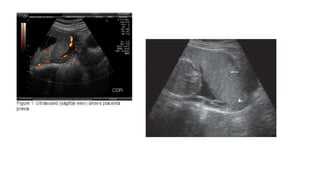

USG menentukan lokasi insersi plasenta, dan menyingkirkan

• USG  insersi pembuluh darah sepanjang OUI